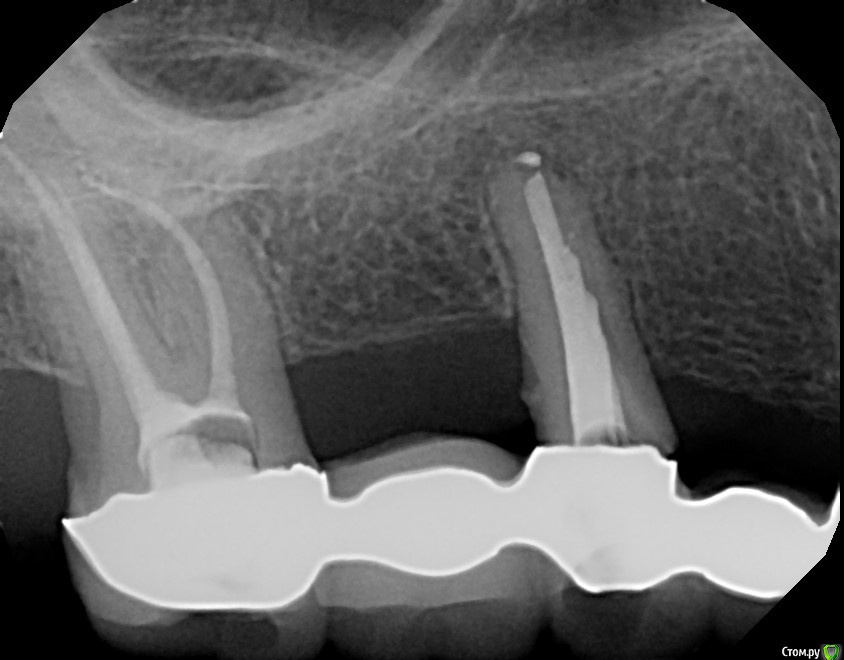

Dirina12 Опубликовано 20 июня, 2017 Автор Поделиться Опубликовано 20 июня, 2017 Эта проблема уже давно. Началось с того что под коронкой заболел зуб. Там был мост и поэтому врач переделал канал через коронку. Болт не ушла. Была такая тянущая боль, как жжёт. Локализации боли не было, болела вся сторона. На снимке ничего не показывало, тогда врач предположил что это средний зуб , распилил мост и удалил зуб. Болт никуда не ушла. И вот 16 июня мне опять открыли зуб и прочистили каналы. Но вот уже 4 й день а зуб болит. Без таблеток не могу( анальгин). Что делать? Может снять коронку и там будет кариес? Может ли кариес давать болт если нерв удалён.? Удалить зуб? Ну уже и так удалили один зуб зря. Первый снимок это уже до удаления среднего зуба. Второй снимок после. Вот тот последний слева ( на снимке) болит. 1 Ссылка на комментарий